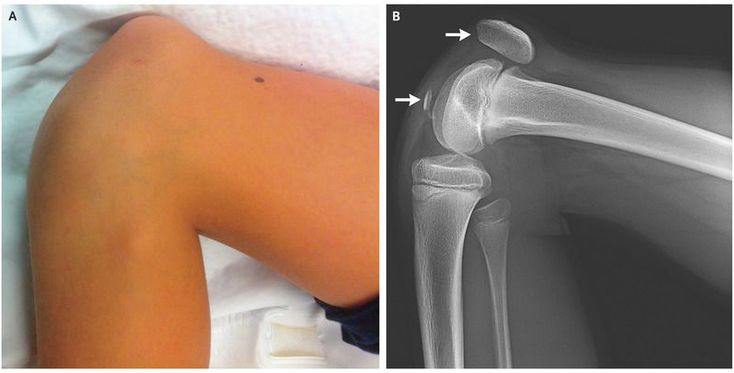

A 9-year-old girl presented with knee pain and inability to extend her leg after landing on her flexed right knee while jumping on a trampoline. Physical examination revealed superior displacement of the patella (Panel A), and a radiograph showed a fracture of the patella at the inferior pole (Panel B; arrows indicate the two points of fracture). These fractures occur almost exclusively in children, before the patella fully ossifies, and usually occur in response to the pressure of a forced load on a flexed knee; the majority involve the inferior patellar pole. The fracture may be difficult to see on a radiograph, especially when the fragment of avulsed bone is small or absent. In this patient, the diagnosis was confirmed on the day of injury during open reduction and internal fixation. The patient was able to return to full activity within 2 months after the injury occurred.